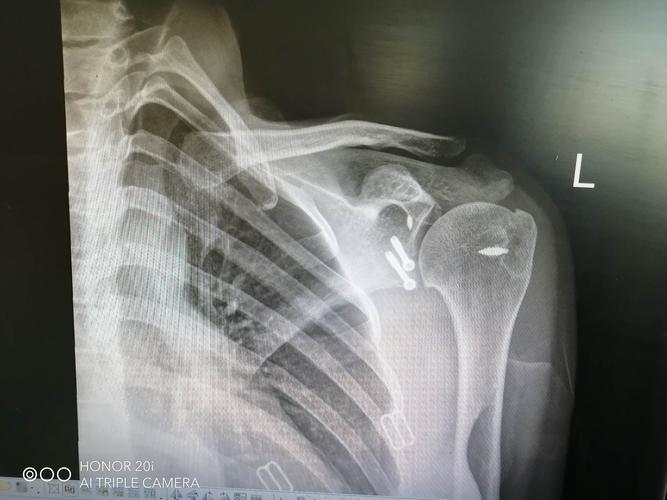

肩胛骨关节盂骨折

肩胛骨关节盂骨折,骨关节炎膝关节畸形

喙突联合1/5关节盂被喙锁韧带,喙肩韧带牵拉向前上形成一个撕脱骨折

一例肩胛盂骨折肩关节镜下骨折内固定术

电击伤致双侧肩胛骨及肱骨头骨折病例分析

肩盂骨折

来源:新乡医学影像 1 肩关节盂环形骨骺约6岁开始化骨.